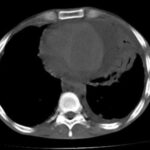

Los antidepresivos tricíclicos, constituyen uno de los grupos farmacológicos con mayor potencial de toxicidad letal en sobredosis debido a la combinación simultánea de efectos neurológicos, cardiovasculares, anticolinérgicos y metabólicos. Aunque…